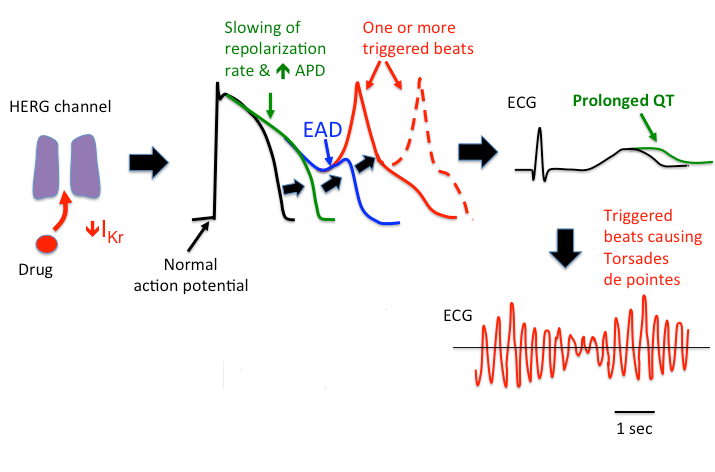

hERG: Block of this channel can slow repolarization, prolong action potential duration, and lead to early after-depolarizations (EADs). This is manifested on an ECG as QT prolongation and can degenerate into a particular type of ventricular arrhythmia, Torsades de pointes.